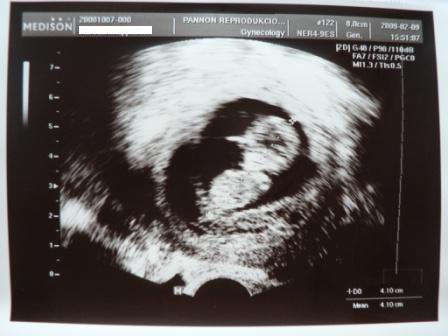

Kép

Íme a mi kis Drágáink. Álló babának úgy járt a keze-lába és bukfencezett, forgolódott egyfolytában, hogy a doktorbácsi alig tudta lemérni. Nagyon édes volt mindkettő, elmondhatatlanul boldog vagyok! :lol: